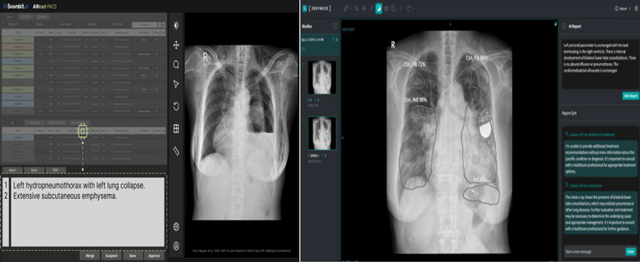

흉부 X-ray 영상을 분석해 예비소견서를 생성하는 소프트웨어인 숨빗AI 'AIRead-CXR'가 3등급 의료기기로 승인을 받은 것이다. 이와 함께 딥노이드(315640) 'M4CXR'도 지난해 11월 자사 M4CXR 임상시험을 마치고 식약처 품목 허가 결정을 기다리고 있다.

단순 질환 의심 부위 표시나 중증도 수치화를 넘어, 57종의 이상 소견을 분석해 전문의 수준의 텍스트 ‘예비소견서’를 직접 작성해 주는 이 기기는 글로벌 의료기기 규제 역사에서도 이례적인 선도 사례로 꼽힌다. 과연 글로벌 의료 강국들과 비교해 이번 국내 첫 허가가 갖는 의미는 무엇일까.